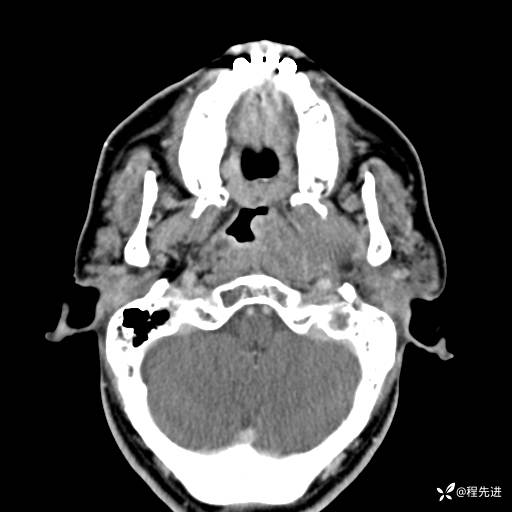

CT平扫:

CTA: